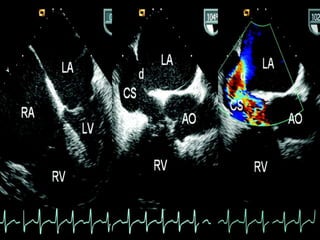

Figure 1. Transesophageal echocardiography revealed both atrial and right ventricular

to the dilated coronary sinus (right) at the near longitudinal plane.

Figure 1. Transesophagealechocardiography revealed both atrial and right ventricular enlargement (left), a defect of the partial coronary sinus (middle), and shunt of the left atrium to the dilated coronary sinus (right) at the near longitudinal plane.